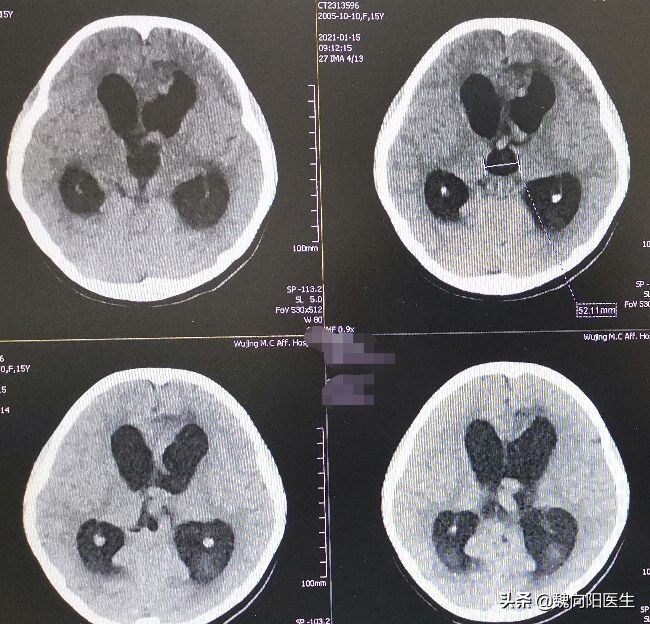

赶紧给小姑娘安排淘CT检查,果不其然,小姑娘的脑室明显增大,脑积水了。

由于小姑娘是动静脉畸形,病变压力比较高,导致脑脊液回流障碍。而且这次脑室出血后,会堵塞蛛网膜膜颗粒,导致脑脊液回收障碍,因此会加重脑积水。

由于小姑娘还正在读初三,长期的脑积水会严重损害小姑娘的认知和智力水平,因此,对于小姑娘的脑积水,建议早期分流手术治疗。